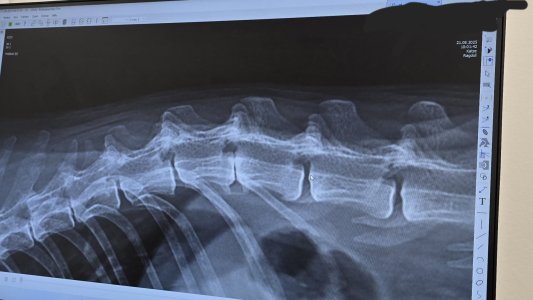

Smee hat höchst wahrscheinlich einen Bandscheibenvorfall.

Leider bildet sich keine Verknöcherung.

Sollte er irgendwann Lähmungserscheinungen zeigen, müssen wir über eine OP nachdenken.